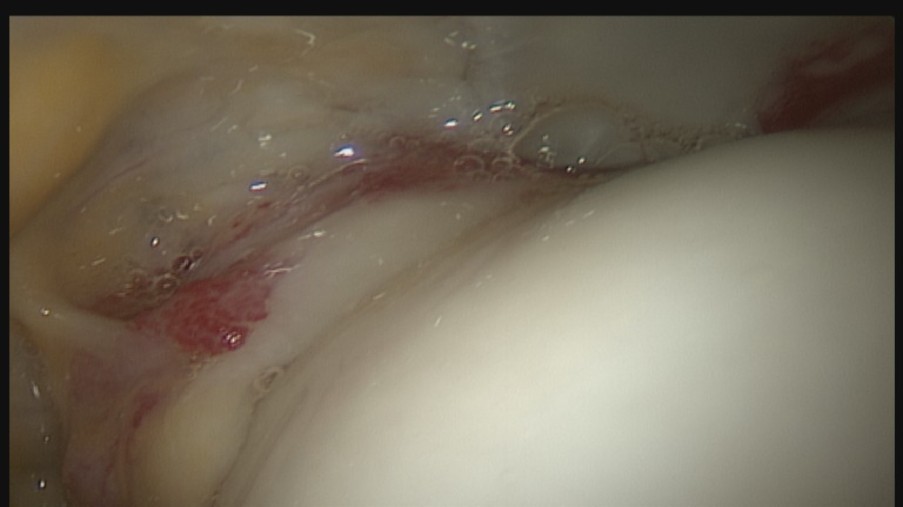

Bei der Arthroskopie handelt es sich um ein minimalinvasives Verfahren, das einen sehr guten Heilungsverlauf besitzt. Bei Erkrankungen und Veränderungen im Hüftgelenk und am Hüftkopf bzw. Schenkelhals kann eine Hüft-Arthroskopie durchgeführt werden.

Im Gegensatz zu der Spiegelung des Kniegelenks ist die Spiegelung des Hüftgelenks ein anspruchsvolleres Verfahren. Dies hängt damit zusammen, dass das Hüftgelenk sich sehr nah an den Gefäßen und Nerven des Beins befindet. Das Operationsteam der LVR-Klinik für Orthopädie Viersen bringt daher eine exakte Kenntnis der Anatomie mit und ist gut geschult.